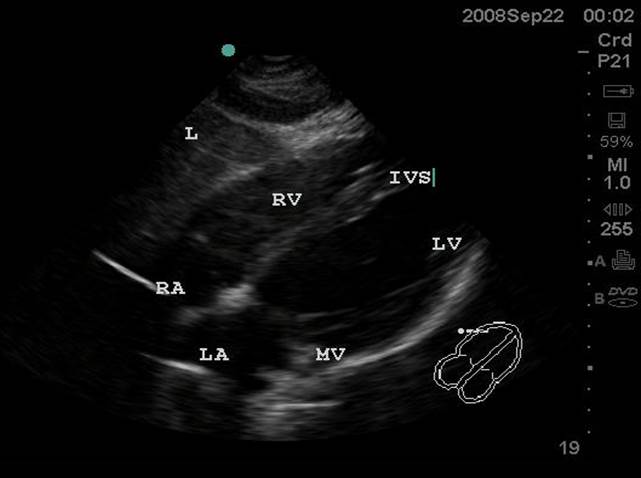

- Figure 1. Subxiphoid View. RA = Right atrium. RV = Right ventricle. IVS = interventricular septum. LV = left ventricle. MV = Mitral valve. LA = left atrium. L = Liver

Video 1. Normal Subxiphoid View - Parasternal Long Axis View: This view captures the flow of blood through the left side of the heart. The apex is to the left of the screen. The mitral valve leaflets are seen and often chordae tendinae connecting them to papillary muscles. Two cusps of the aortic valve (usually the non-coronary and right coronary cusp) are seen. The left ventricular outflow tract (LVOT) is the term for the aortic root and proximal ascending aorta. A portion of the right ventricle is seen in the near field.